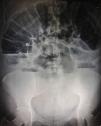

Abdominal X-rays (Figs. 1 and 2) showed significant distension of the intestinal loops, interloop oedema, absence of gas in the rectal ampulla, fluid-air levels and the image of a foreign body in the upper left quadrant.

Given the above, a diagnosis of intestinal occlusion secondary to a foreign body was made, and therefore an exploratory laparotomy was performed. The procedure was reported complication-free, finding a piece of textile lodged in the upper left quadrant, hardened and adhering to the intestinal loops, with friable, oedematous surrounding tissue, and peritoneal reaction fluid estimated to be approximately 100ml.